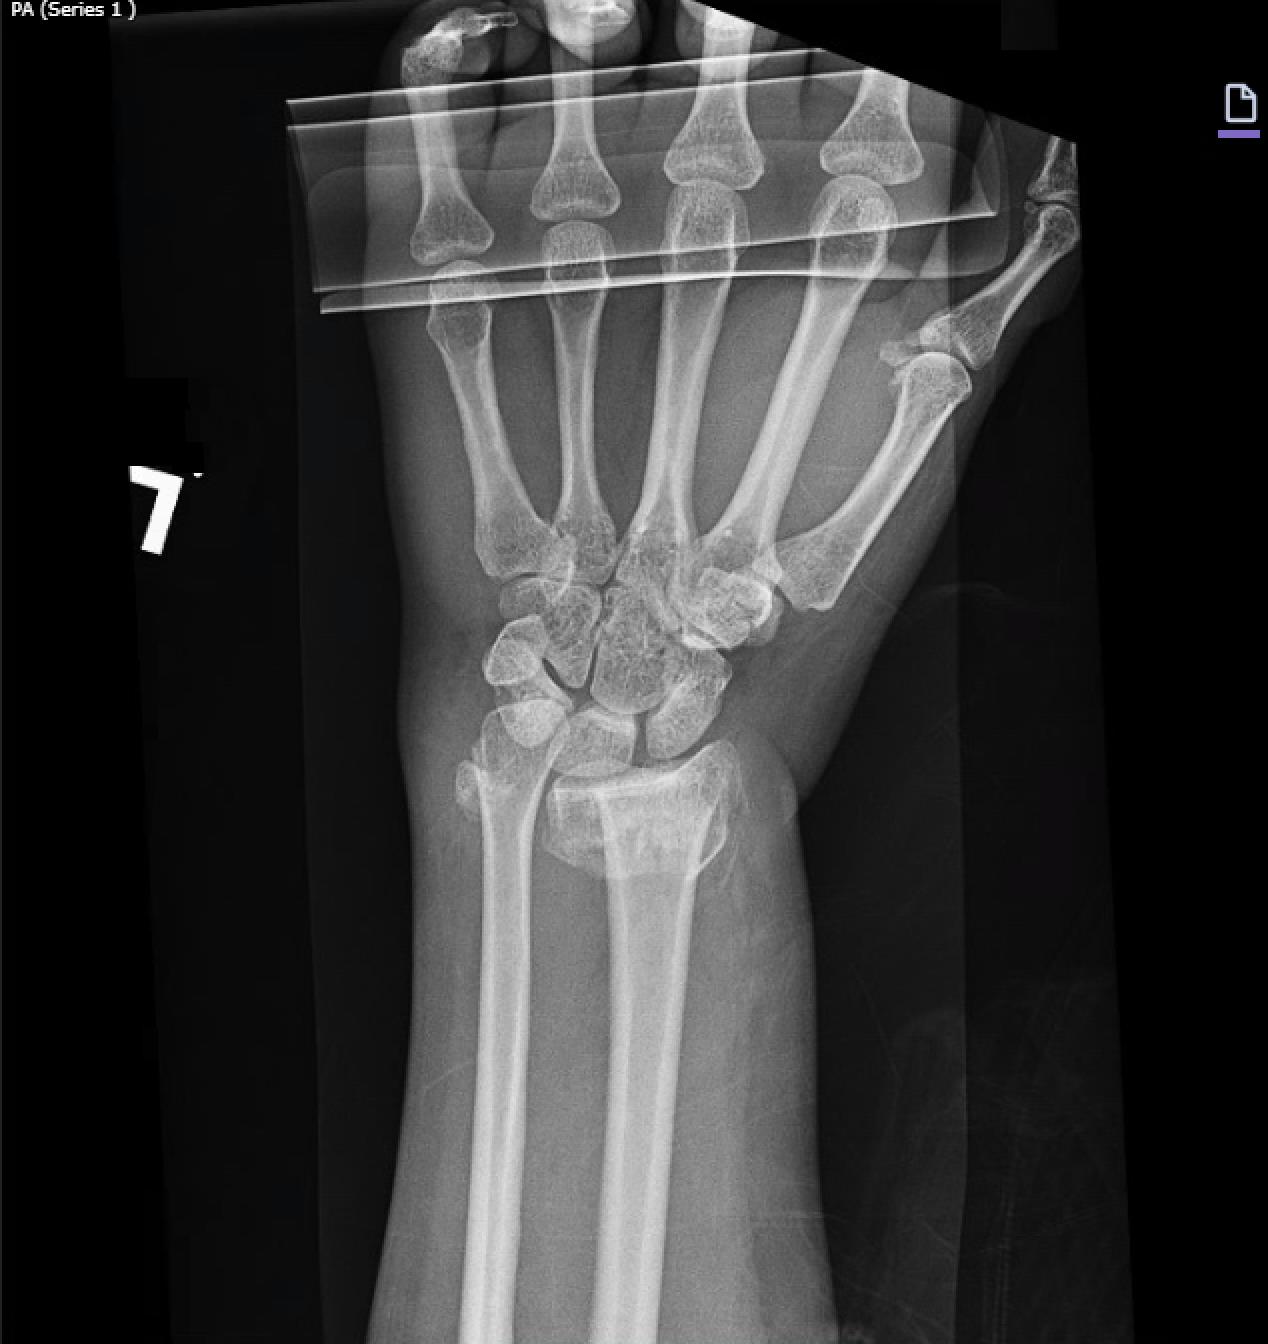

• Average age was 55 years, median follow-up was 24 months, and the most common use was in comminuted (92%) intra-articular (92%) distal radius fracture caused by fall (58%), or motor vehicle collision or motorcycle collision (27%). A minority of patients had open fractures (16%) and most were cases of polytrauma (65%). Median time from placement to DBP removal was 17 weeks (mean, 119 days). At final follow-up, mean wrist ROM was 45° flexion, 50° extension, 75° pronation, and 73° supination. Mean DASH score was 26.1, and mean QuickDASH score was 19.8. The overall rate for any complication was 13%; the most common was hardware failure (3%) followed by symptomatic malunion or nonunion (3%), and persistent pain after hardware removal (2%).

• Dorsal bridge plating was found to be used most commonly in intra-articular, comminuted distal radius fractures with overall functional wrist ROM, moderate patient-reported disability, and a 13% complication rate at follow-up.